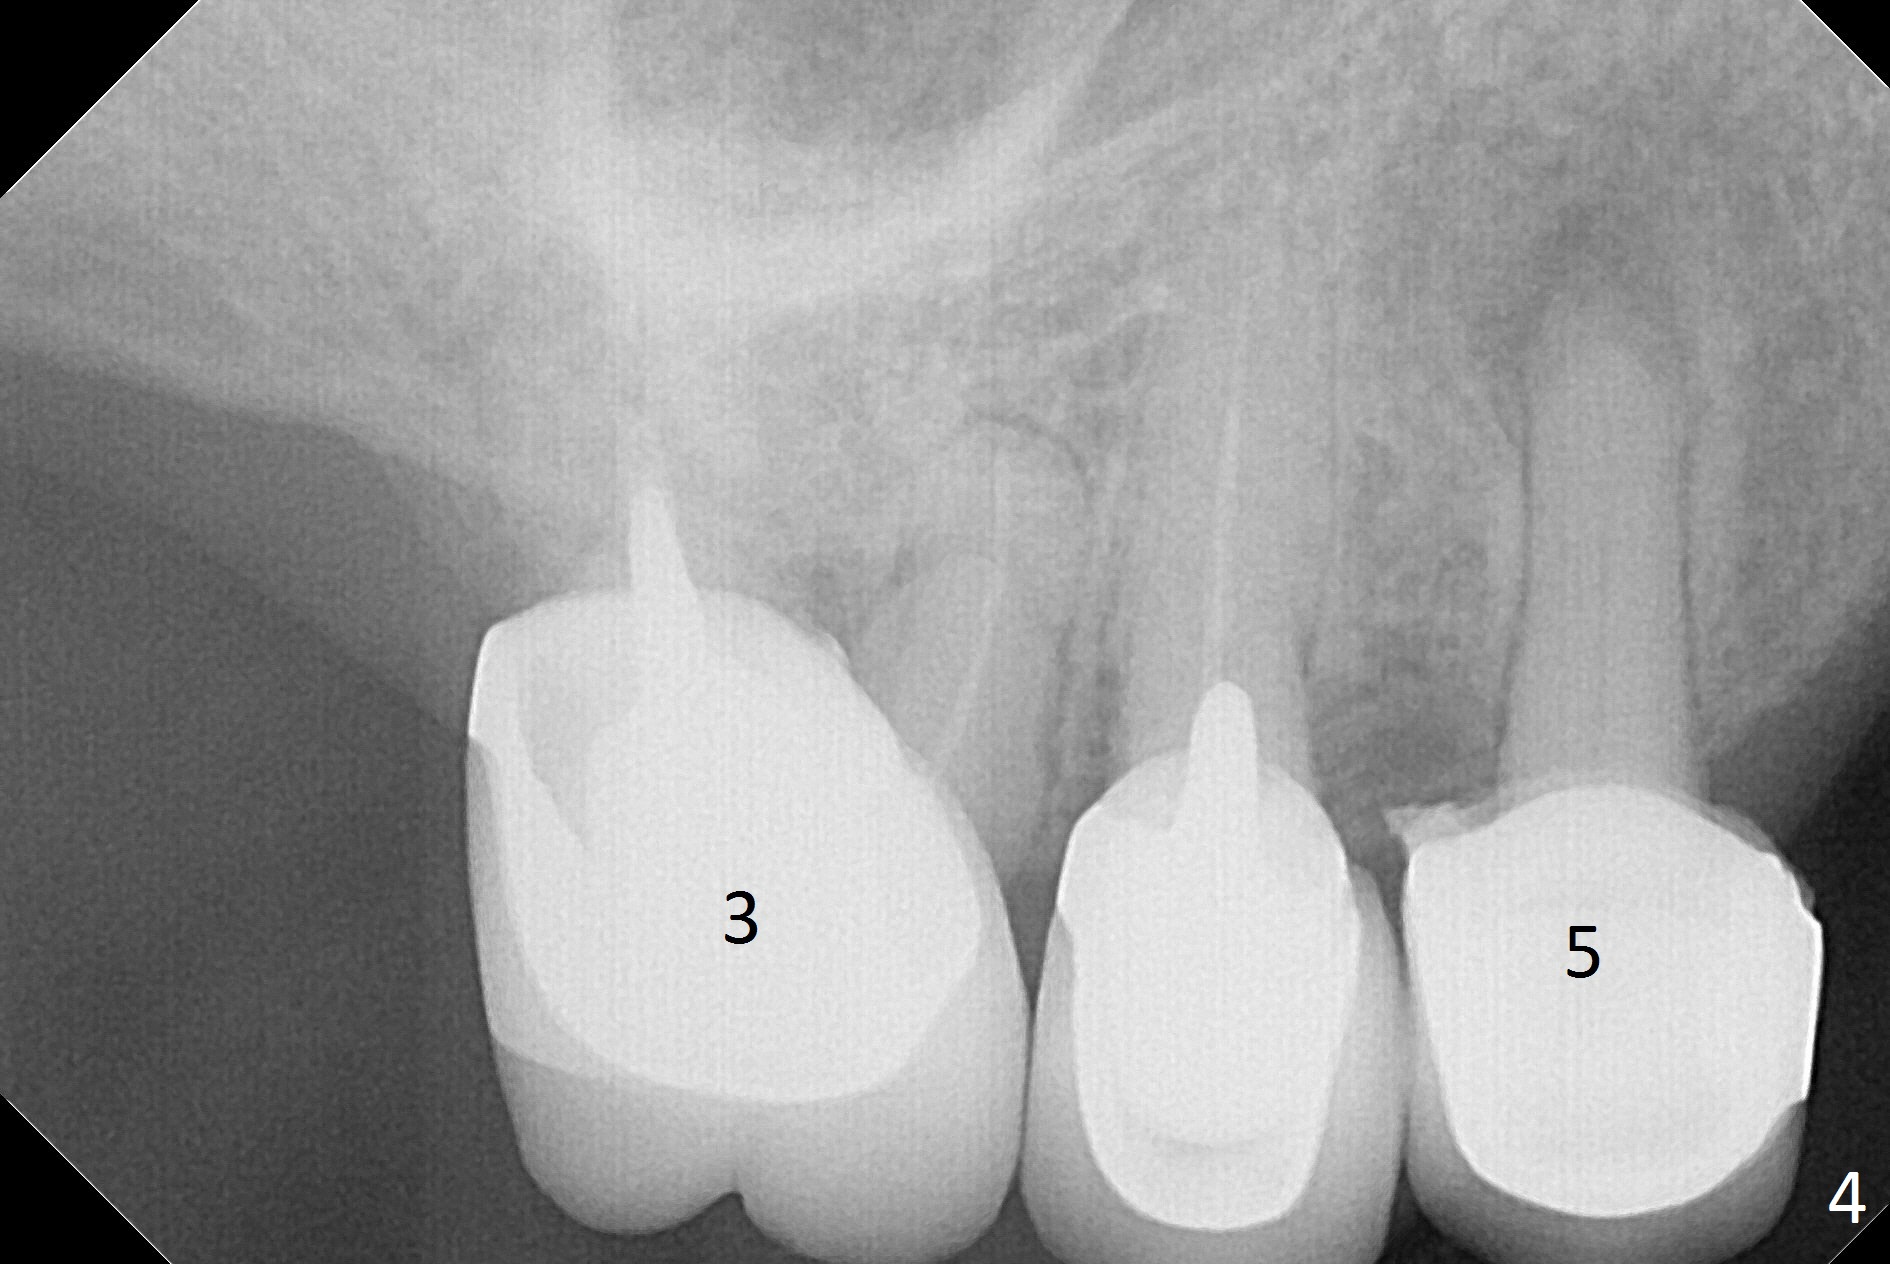

A 62-year-old woman has poor dentition (Fig.1). The most critical area is the upper left anterior: #9-11, which were extracted 4 months earlier (Fig.2). Implants will be placed at #9 and 11 with fabrication of a provisional bridge (Fig.3). After incision, use Magic Split to start bone expansion, followed by micro-osteotomes 1 and 1.5 mm and Magic Osteotomes 3 and 3.8 mm. If the transition between 1.5 and 3 mm osteotomes is not smooth, apply RT2. Place the smallest bone-level implants (for hybrid denture in the future) with gold coated abutments. There should be no interference with or without the partials and in and out. Next step should be removing splinted crowns at #26 and 27 (Fig.1), RCT for #27 and immediate implant at #26 (Fig.5,6 Metronidazole). In fact the splinted crowns at #26 and 27 were lost last week. The patient thinks that she needs 2 implants. The next one is to remove the crown at #5 for RCT (Fig.4).